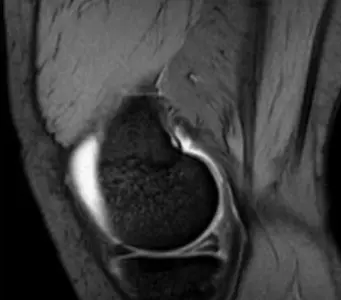

Q4/ 7 years old boy, noticed by his parents that he had limping over last 3 months. x-ray obtained. Whatโs the diagnosis?

- Pertheโs disease

Diagnosis: Legg-Calve-Pertheโs Disease

- Collapse โ Fragmentation - flattening (coxa plana)

A 7 year old boy presented to emergency room with painful limping right lower limb. Clinically he has limitation of abduction and internal rotation movement at his right hip.

Q1: Mention two abnormal findings:

- Collapse and fragmentation of epiphysis

- Sclerosis

Q2: What is the most probable diagnosis?

- Legg-Calve-Pertheโs disease

X-ray findings in Perthes disease:

- Fragmentation and collapsed epiphysis

- May initially look normal in x-ray